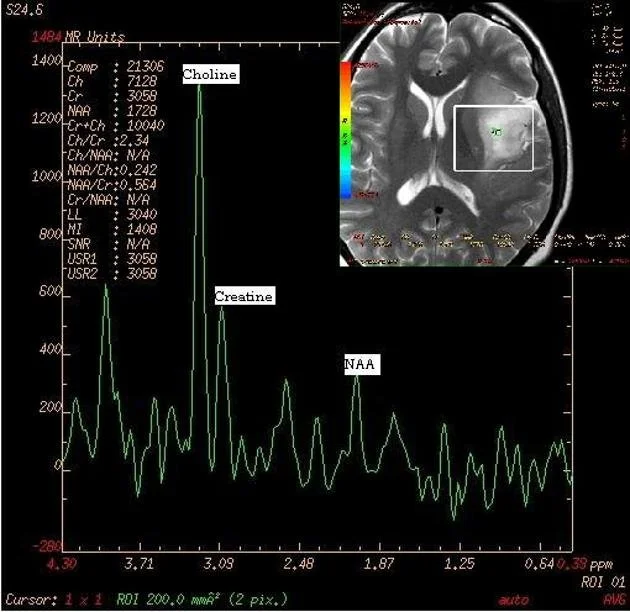

MRS provides biochemical information of compounds present in human tissue and cells. Human brain contains hundreds of metabolites but proton MRS can only detect a few of them as least multi-molar concentrations are necessary for the metabolites to be detected. The major brain metabolites detected are choline (Cho), creatine (Cr), N-acetyl aspartate (NAA), lactate, myo-inositol, glutamine and glutamate, lipids, and the amino acids leucine and alanine.

N-Acetyl Aspartate (NAA) is an amino acid found exclusively in neurons. It is regarded as a non-specific marker and is thought to be involved in Coenzyme A interactions and lipogenesis within the brain. It is a marker of neuronal viability. Normal NAA concentration is in the range of 8-9 mmol/kg in healthy adult brain. Concentrations are decreased in conditions leading to axonal injury or neuronal loss. NAA is also decreased in other conditions such as neoplasm, infarction, and inflammatory conditions such as multiple sclerosis. NAA peak is seen at 2.0 ppm (parts per million) on MR spectra.

The Choline (Cho) peak is a heterogeneous peak representing various choline-containing compounds such as acetylcholine, phosphocholine (lecithin), glycerophosphocholine, and various other intermediates of phospholipids metabolism. It is an indicator of cell density and cell wall turnover.  Elevated levels are found in some tumors, especially malignant ones, and in certain demyelinating diseases. Choline resonance presents at 3.22 ppm. Studies have shown there is also a direct association between Cho and levels of Ki-67, a protein expressed in all phases of the cell cycle except GO that serves as a good marker for cellular proliferation. This observation makes Cho a reliable predictor of cellular activity in tumor tissue.

Creatine (Cr) is basically related to cell energy pathways. It is both the substrate and product of creatine kinase. Creatine reflects the energy potential available in brain tissue. Its concentration in normal brain remains very high and stable due to high metabolic energy needs of brain cells. Its peak is noticed at 3.0 ppm. Creatine-Choline ratios are an important indicator of disease states such as demyelization.